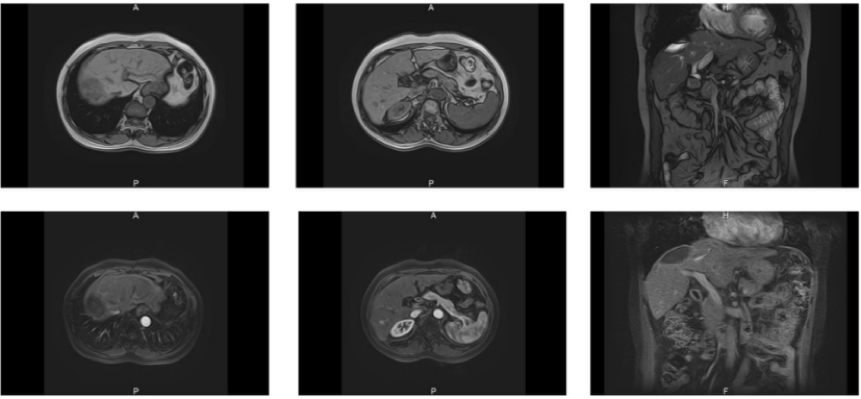

2019年7月25日上腹部CT增强提示:肝脏大小形态正常,肝S7段见类圆形异常密度影,大小约60mm×55mm,边界欠清(图1)。

图1.2019年7月25日上腹部CT